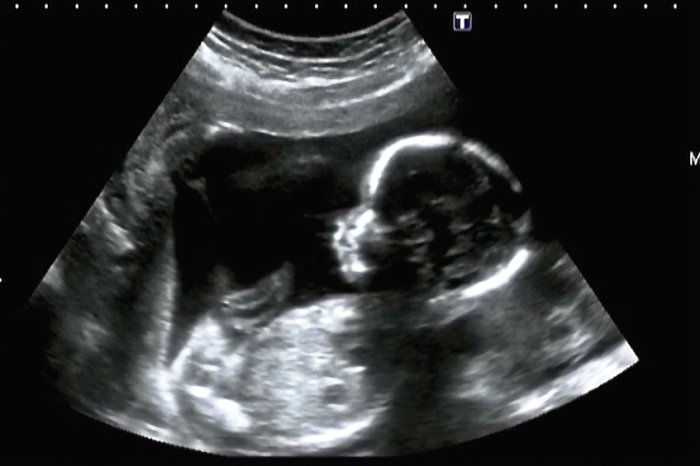

O diagnóstico do crescimento fetal se baseia na comparação de dados antropométricos do feto, obtidos por meio de ultrassom, comparados com curva de crescimento intrauterino obtida de recém-nascidos vivos, de diferentes idades gestacionais, considerados "normais" por provirem de gestações sem patologias detectadas.

Outro método para verificar o crescimento fetal é a ultrassonografia. Com o intuito de estimar o peso fetal, o ultrassom pode ser usado para medir a cabeça, o abdome e o fêmur do bebê. Com essas medidas, o médico pode estimar o peso do bebê e comparar o valor encontrado com curvas de referência. O ultrassom também pode ser usado para determinar a quantidade de líquido amniótico que está no útero. Uma baixa quantidade de líquido amniótico pode sugerir uma restrição de crescimento intrauterino.